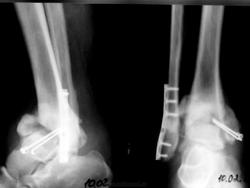

Пациентке 50 лет, в марте 2011 получила бытовую травму, при поступлению в одну из ЦРБ Нижегородской области был диагносцирован трехлодыжечный перелом, наружный подвывих стопы (рентгенограммы 1). Поскольку боковая рентгенограмма сделана с ротацией, никто не обратил внимания на передний отдел метаэпифиза б/берцовой кости. Пациентке налажено скелетное вытяжение (рентгенограммы 2,3), на боковом снимке видно повреждение переднего отдела метаэпифиза, но внимание на это не обращается, выполняется стандартный остеосинтез наружной и внутренней лодыжек (рентгенгограммы 4), опять же ни о кого не возникает никаких вопросов, а именно: почему дисконгруэнтна суставная щель, стопа в переднем подвывихе и в эквинусе. В августе пациентка приходит на контроль, и уже отчетливо виден дефект переднего отдела метаэпифиза б/берцовой кости, смещение костного фрагмента метаэпифиза кпереди и передний вывих стопы, но никаких мероприятий не проводится. Вчера, 9.02 пациентка все же доходит до нашего института, и мы видим такую картину (рентгенограммы 5,6): дефект переднего края дистального метаэпифиза б/берцовой кости, костный фрагмент смещен кпереди, некротизирован (фактически это секвестр), стопа в положении переднего вывиха, разрыв дистального межберцового синдесмоза, нестабильность металлоконструкций в б/берцовой кости (отчетливо видна резорбция), асептический некроз блока таранной кости. Прогноз неблагоприятен: артродезирование г/стопоного сустава, вопрос только в выборе метода, аппаратный артродез, либо ретроградный интрамедуллярный.